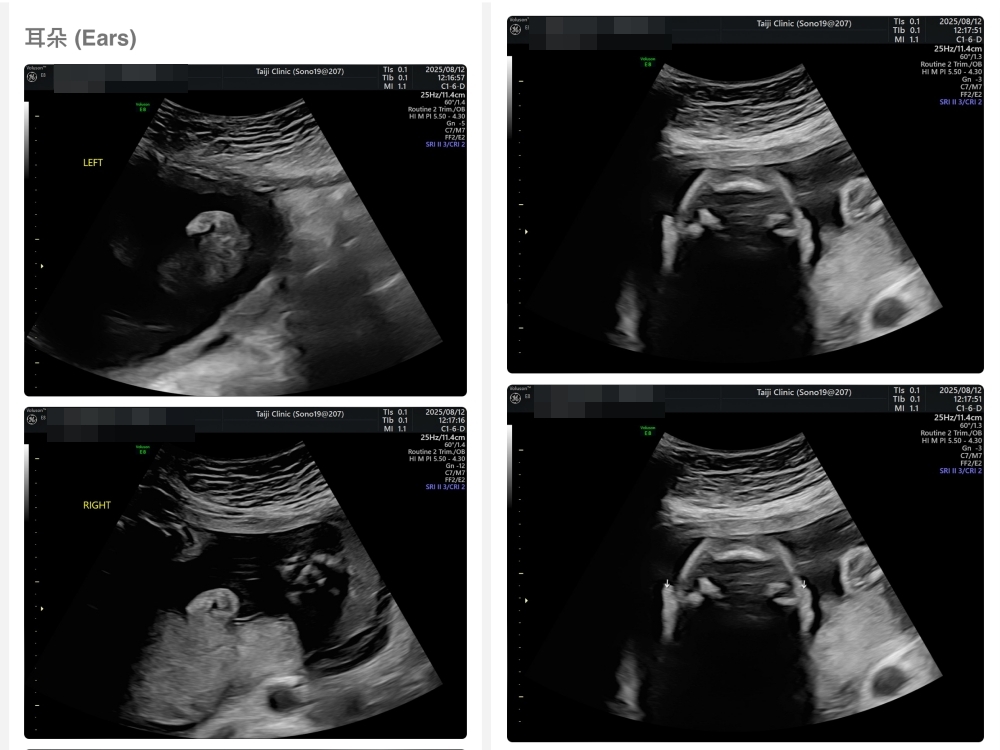

▲離開診所後會收到MAIL,我們14:05離開,大約是16:45收到mail,裡面會有滿滿的超音波照片,紀錄的很詳細!也會提供紙本的報告,可以給日後產檢的醫師做參考👌